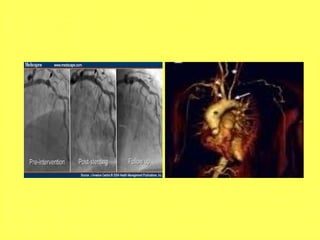

ARTERIOGRAPHY

Helps specially in in arteries that cannot be

biopsied easily like Aorta, Coronary artery,

Mesentric vessels

Presence of vascular patency, Aneurysms

• Aortic Angiography- Takayasu’s

• Cerebral Angiography- Isolated CNS vascultis

• Renal Angiography- PAN

• Coronary Angiography- Kawasaki’s

• Lower limb arteriography-Buerger’s Disease

(TAO)